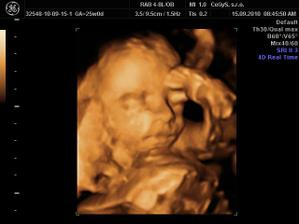

Náš anjelik🙂